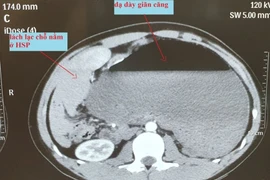

Hiếm gặp: Dạ dày của nam thanh niên tự xoắn 180 độ, lách và thận nằm lạc chỗ